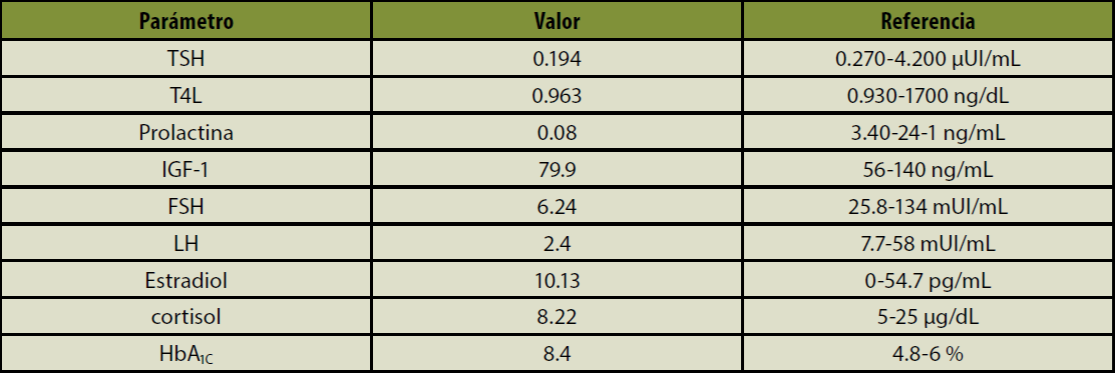

Tabla 1 Estudios de laboratorio

FSH: hormona foliculoestimulante; HbA1c: hemoglobina glucosilada; IGF-1: factor de crecimiento similar a la insulina, tipo 1; LH: hormona luteinizante; T4L: tiroxina libre; TSH: hormona estimulante de tiroides; PRL: prolactina.